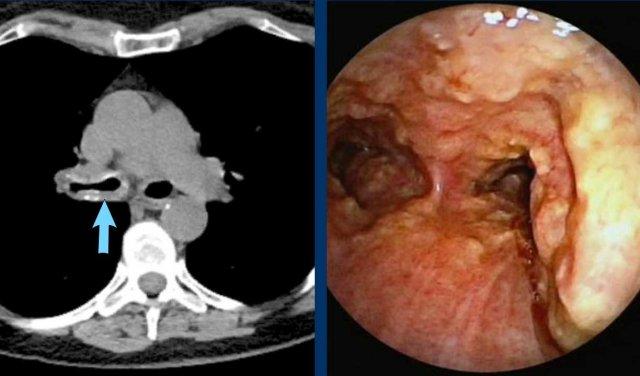

Hình ảnh

Khối khu trú không đều xâm lấn thành khí quản và tổ chức quanh khí quản ở nam giới 66 tuổi.

Giải phẫu bệnh:

Ung thư biểu mô tế bào vảy.

Hẹp lòng khí quản nặng do khối khu trú ở nữ giới 48 tuổi.

Giải phẫu bệnh: Ung thư biểu mô tuyến nang khí quản.

Khối thâm nhiễm lan tỏa không đều với đoạn dài dày thành xâm lấn trung thất ở nữ giới 51 tuổi.

Ung thư biểu mô tuyến nang.

Hình ảnh nội soi phế quản của ung thư biểu mô tuyến nang khí quản gây tắc nghẽn.